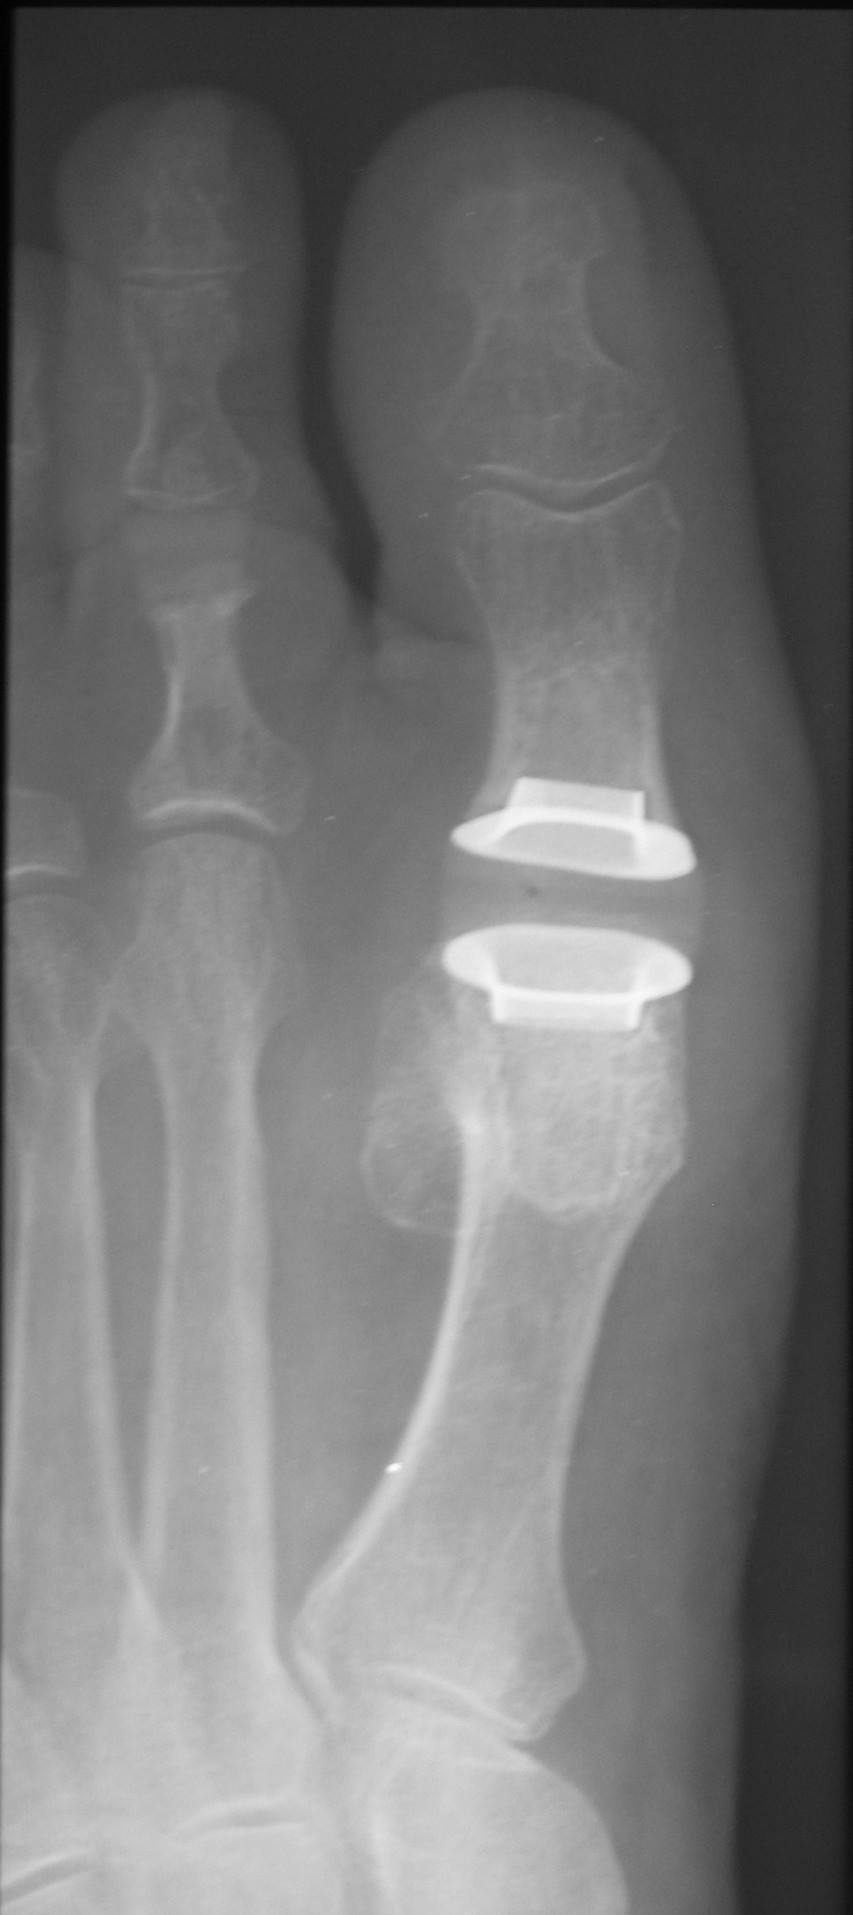

From www.hmpgloballearningnetwork.com

A Closer Look At The Primus First MPJ Implant What Is A Joint Implant  During knee replacement surgery, an orthopaedic surgeon will resurface your damaged knee with artificial components, called implants. Total joint replacement is a surgical procedure in which parts of an arthritic or damaged joint are removed and replaced with a metal, plastic, or ceramic device called a prosthesis. Thinking about a total knee replacement? Makes an incision over the knee. There. What Is A Joint Implant.